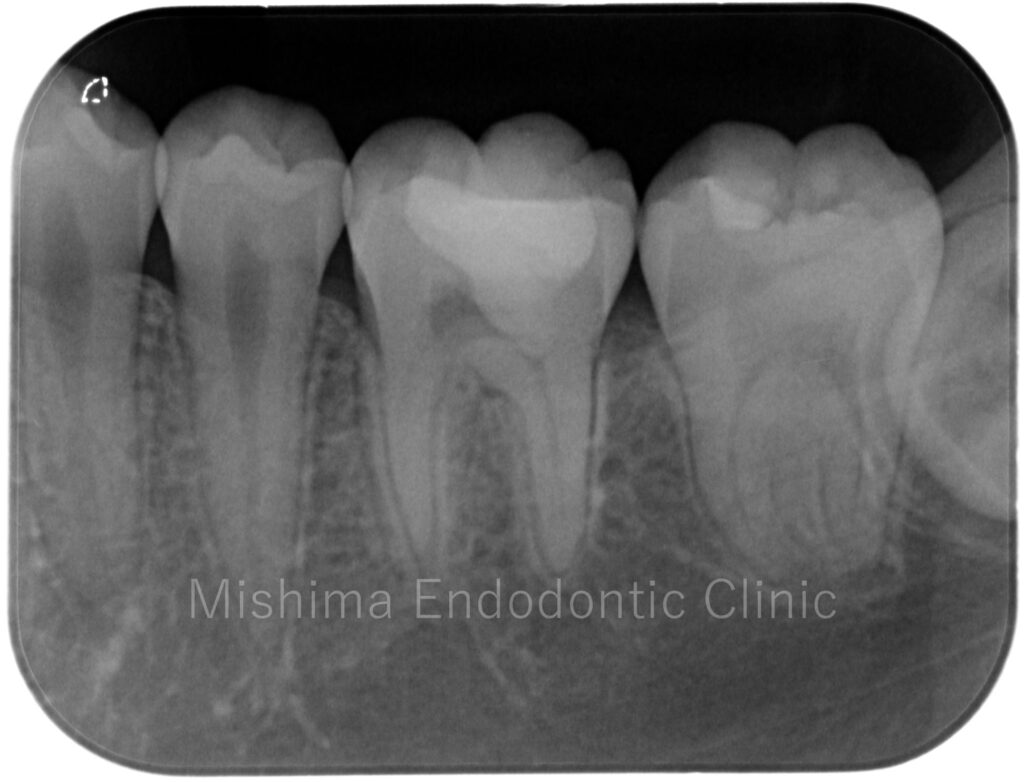

| 治療内容 | 咬合面にCRにて修復されており、CR下にてカリエスを認めた。歯髄診査にて歯髄は正常歯髄と診断。カリエスを除去していくと露髄を認め、壊死歯髄を除去、部分断髄し、バイオデンティンにて覆髄、CRにて最終修復まで行った。 |

術後 1年